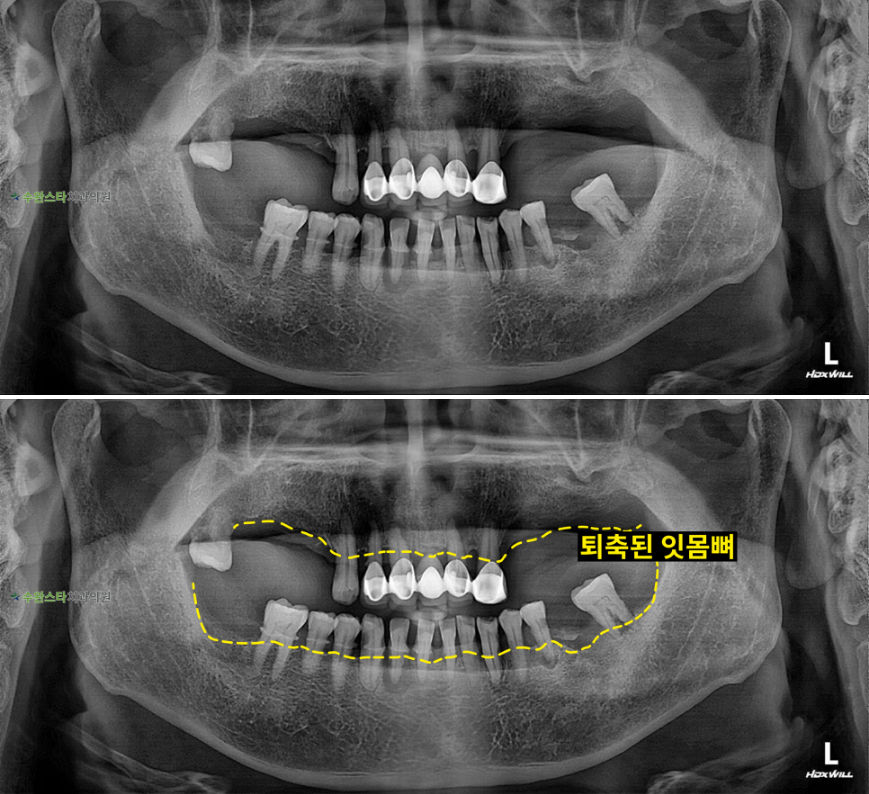

내원 시 파노라마 사진입니다.

어금니 쪽 잇몸뼈가

위 아래 모두 많이

퇴축된 모습입니다.